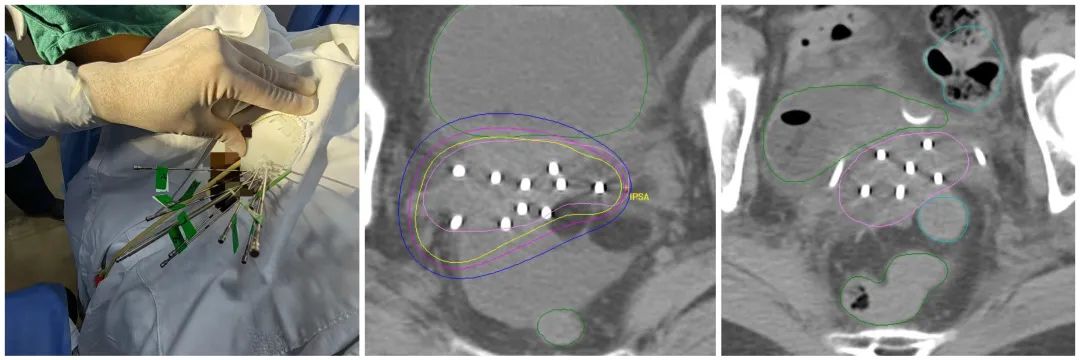

考虑到患者肿瘤大侵犯广泛,膀胱和盆腔侧壁高位侵犯,外照射结束后宫颈及双侧宫旁盆壁仍有明显肿瘤残留,因后装治疗进针路径通常为阴道,插值难度较大,较难布针布源满意达到合适的放疗剂量分布,同时患者对疼痛非常敏感,对后装治疗很抗拒。经治疗小组讨论后,与患者及家属沟通,拟予患者实施人工智能3D打印模板引导三维无痛插值后装治疗,鉴于是无痛和精准的治疗,患者和家属考虑愿意接受。

我们治疗上首先对患者进行模拟定位,制定出3D打印虚拟计划并设计针道,设计患者个体化3D后装模板,并制定周密个性化的精确放疗计划。麻醉科进行麻醉评估无禁忌症后,在B超实施超声引导给予患者行3D后装模板插植施源器植入。

后予患者行定位CT扫描,调整插值针位置深度,实时勾画三维后装靶区,放疗物理师制定出放疗计划,验证计划核查无误后,后装技师开始实施后装放疗。